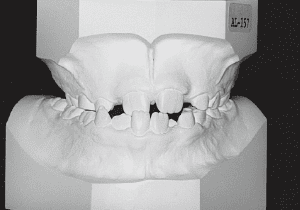

1 At start of treatment 7-21-’88

A case of diverted and cross bite during the deciduous dentition. Despite early treatment, the deviation progressively worsened with age, necessitating surgical treatment. At the initial visit, the patient had a deciduous dentition, and observation was planned (3). With the eruption of the permanent incisors, the mandible shifted slightly to the right, resulting in a cross bite (1) At this point, asymmetry can be confirmed in the front view. However, it is slight. The cephalometric X-ray reveals a structure with a slightly dominant mandible, but asymmetry in the mandibular ramus is not observed.